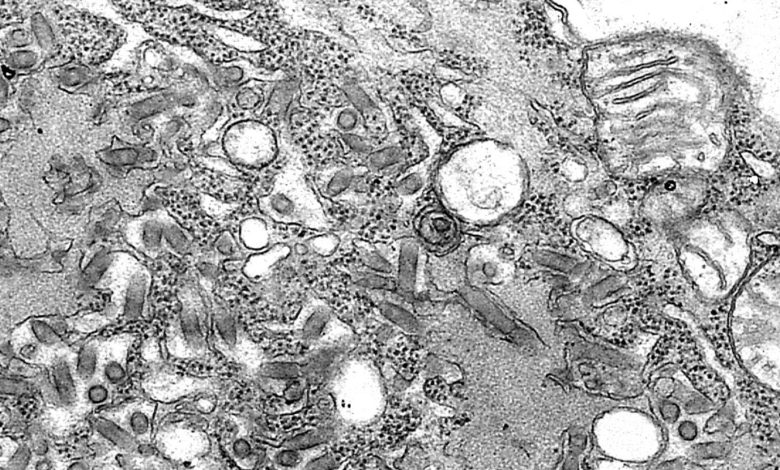

Спустя примерно пять недель после трансплантации у реципиента из Мичигана развились симптомы, характерные для бешенства. Анализы его слюны, кожи и других жидкостей, отправленные в CDC, подтвердили наличие РНК вируса бешенства. Поскольку сам пациент не подвергался нападению животных, эпидемиологи изучили историю донора. Исследование архивного образца биопсии почки донора дало положительный результат на РНК вируса, окончательно подтвердив путь заражения. Пациент скончался на седьмой день госпитализации.